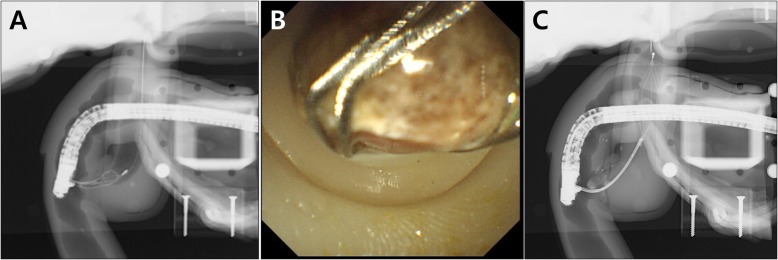

Bile duct stone extraction was also successfully implemented using the CBD dilation module. Before the procedure, we inserted a 12 mm cholesterol stone, into the module, which was obtained from a surgically resected human gallbladder. After capturing the stone by a conventional basket catheter (Flower Basket V™, Olympus Co.), the stone was pulled out from the ampulla by using a flip down technique (Fig. 7a and b). The ampullary orifice of the module was well-extended without sphincterotomy, and it was not damaged after the stone removal. Mechanical lithotripsy with a lithotripsy basket catheter (Trapezoid™ RX, Boston Scientific Co., Natick, MA.) was also successfully implemented using the distal stricture and proximal dilation CBD module (Fig. 7c).